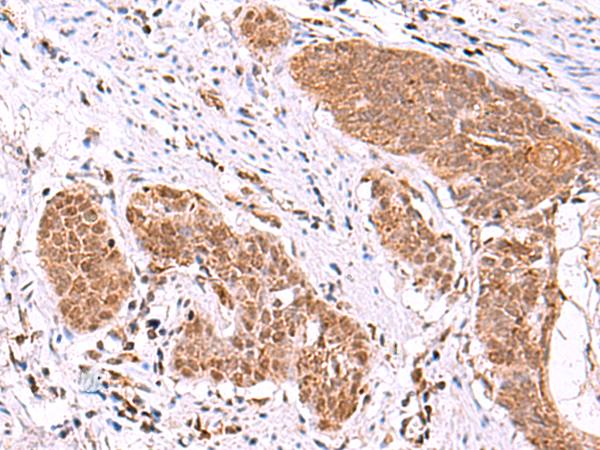

分类: 科研抗体货号: P10149别名: FPS; FPPS; POROK9应用: IHC反应种属: Human, Mouse, Rat